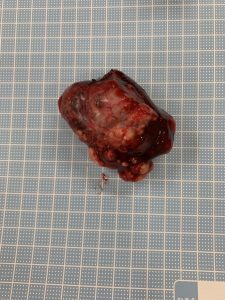

腹部正中切開により肝臓腫瘍路露出し、尾状葉を腫瘤と共に切除した。

マージン部に腫瘍性の病変は認められず、腫瘤の摘出状態は良好と考えられますが、進行した転移性の病変が形成されていることから、引き続き、転移の拡大について注意が必要です。